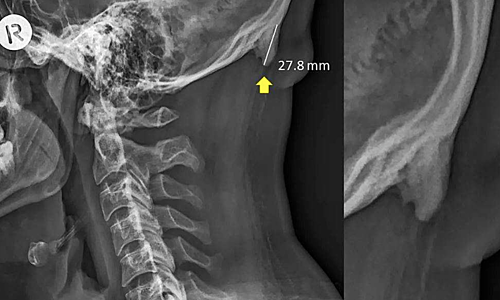

Ảnh chụp chiếc gai đằng sau cổ của một nam bệnh nhân 28 tuổi. Ảnh: David Shahar/Mark G L Sayers/Scientific Reports/CC.

Các nhà khoa học từ University of The Sunshine Coast (Australia) cho biết càng nhiều bệnh nhân trẻ đến bệnh viện với những chiếc gai nhỏ phía sau cổ. Thông thường, chúng có chiều dài khoảng 2,6 cm nhưng một số trường hợp có thể lên đến 3,1 cm.

Trên Scientific Reports, các nhà khoa học University of The Sunshine Coast cho biết hiện tượng hộp sọ "mọc" gai trên còn được gọi là đáy gai nhô bên ngoài vùng chẩm (EEOP), chủ yếu xuất hiện ở người già. Tuy nhiên, khảo sát trên 1.200 tình nguyện viên 18-86 tuổi cho thấy 33% bị EEOP, trong đó phần lớn thuộc nhóm nam giới 18-30 tuổi. Các nhà khoa học cho biết tình trạng này bắt đầu xuất hiện vào những năm 1990 và ngày càng phổ biến.

Hiện tại, các nhà khoa học chưa tìm ra được mối liên hệ chính xác nhưng cho rằng việc sử dụng các thiết bị điện tử ở tư thế sai dẫn đến tình trạng này. Ngồi hàng giờ với chiếc cổ bị quẹo hoặc cúi xuống quá thấp có thể gây áp lực cho nền sọ và cơ thể sẽ phản ứng lại bằng cách xuất hiện gai nhỏ để đỡ.